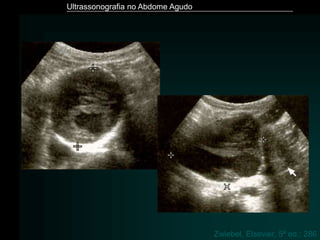

Zwiebel, Elsevier, 5ª ed.: 286

Ultrassonografia no AbdomeAgudo Zwiebel, Elsevier, 5ª ed.: 286